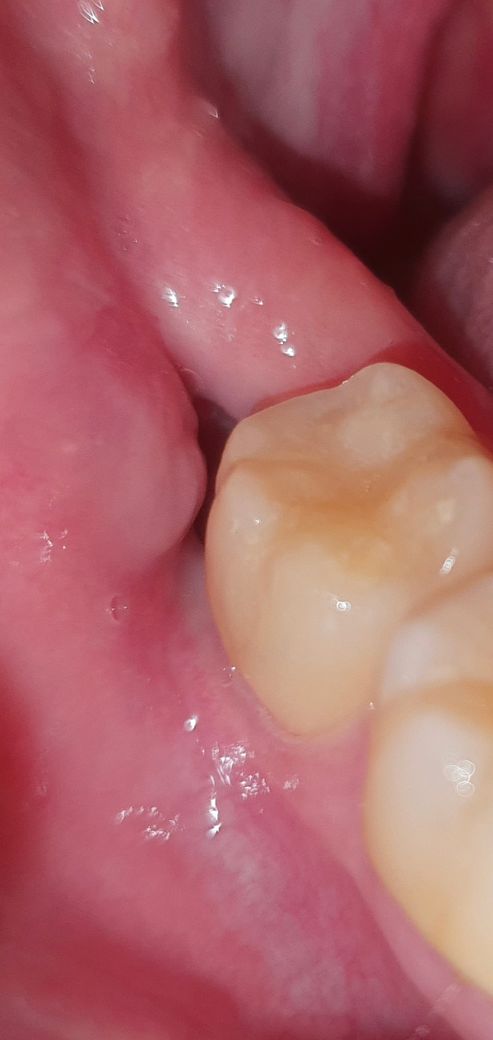

사랑니 뺀뒤 잇몸에 대한 질문입니다(사진 포함)

1.원래 붙어있던 볼쪽 잇몸이 치아와 떨어진것 같습니다.

2.또한 안쪽에 검정색으로 딱지로 추정되는 것이 매우 낮게 존재하고있어 구멍난 부위까지 잇몸이 차오를지 의문입니다.

정상적으로 잇몸이 모두 차오르고 회복될것처럼 보이지가않습니다. 상처라는것이 딱지가 존재하는 곳까지만 회복되는것 아닌가요? 선생님들의 의견이 필요합니다

정상적인 회복과정입니다. 즉 볼쪽 잇몸이 치아와 떨어진 것이 아닙니다. 혈병이 이뤄진 다음에 섬유화를 거치고 나중에 뼈와 잇몸으로 바뀔 것으로 보입니다. 상피가 어느정도 덮히는데도 최소 2주~ 한달 이상 걸리기 때문에 해당 공간이 있는 것은 당연합니다. 통증이나 불편감이 없다면 자연스럽게 주변 잇몸과 조화를 이룰 것으로 보입니다.

사진상으로 사랑니를 뺀지 얼마 되진 않은것같습니다. 6개월이상 되진 않은것같고, 길다면 1-2달정도 된것같습니다.

원래 발치후 처음에는 공간이 보일 수 있습니다. 하지만 시간이 더 지나면 잇몸이 차올라오기 때문에 너무 걱정하실 필요는 없습니다. 감사합니다.